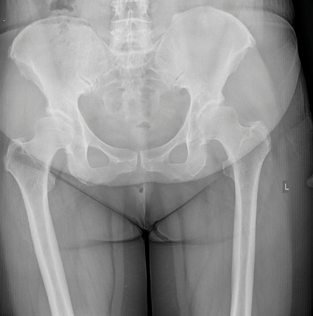

Το πρώτο βήμα κατά τη λήψη της απόφασης για την αντικατάσταση ισχίου είναι να συναντήσετε τον χειρουργό σας για να δείτε εάν είστε υποψήφιος για χειρουργική επέμβαση ολικής αρθροπλαστικής ισχίου. Ο χειρουργός σας θα πάρει το ιατρικό ιστορικό σας, θα κάνει μια φυσική εξέταση και θα ζητήσει ακτινογραφία του ισχίου σας. Ακόμα κι αν ο πόνος είναι έντονος και οι ακτινογραφίες δείχνουν προχωρημένη αρθρίτιδα της άρθρωσης, η πρώτη γραμμή θεραπείας είναι σχεδόν πάντα μη χειρουργική. Αυτό περιλαμβάνει απώλεια βάρους εάν χρειάζεται, πρόγραμμα άσκησης, αντιφλεγμονώδη φάρμακα, ενέσεις ή νάρθηκες. Εάν τα συμπτώματα συνεχιστούν παρά αυτές τις θεραπείες και με επιβεβαιωτικές ακτινογραφίες, τότε μπορείτε να εξετάσετε το ενδεχόμενο χειρουργικής επέμβασης.